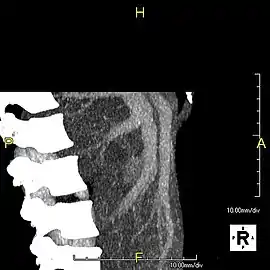

Axial CT image showing anomalous hepatic veins coursing on the liver's subcapsular anterior surface[66]

Maximum intensity projection (MIP) CT image as viewed anteriorly showing the anomalous hepatic veins coursing on the anterior surface of the liver

Lateral MIP view in the same patient as previous image